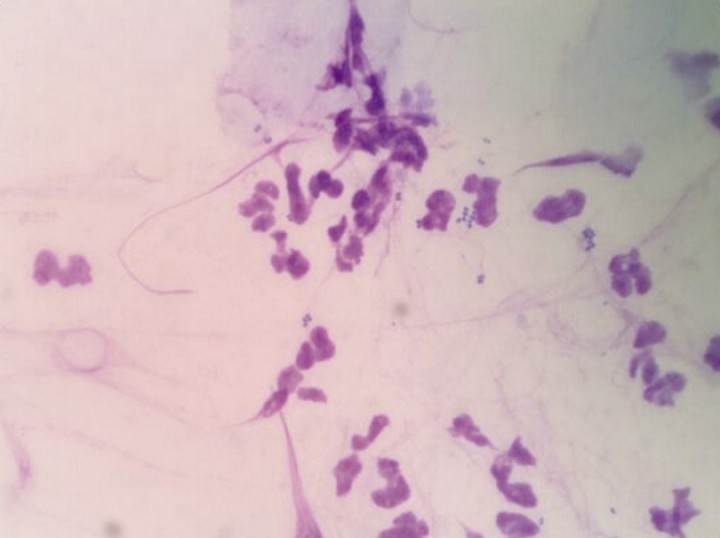

2. Tratar las infecciones secundarias, siendo preciso un tratamiento prolongado (meses) en casos de pioderma profunda, la cual se evidencia en el 94% de los pacientes con dermatitis acral (Figs. 6 y 7).[ Medleau L, Hnilica KA. Capítulo 13: Otras dermopatías del perro. En: Dermatología de pequeños animales, Madrid, Elsevier España, 2007; 327-342. , Miller WH, Grifin CE, Campbell KL. Dermatosis psicogénicas. En: Muller & Kirk: Dermatología en pequeños animales, Buenos Aires, Inter-médica; 2014; 712-724. ] Se recomienda en cualquier caso realizar el cultivo y antibiograma de tejidos profundos obtenidos mediante biopsia, especialmente si no hay una buena respuesta a un tratamiento antimicrobiano empírico. La presencia de gérmenes multirresistentes es frecuente, siendo preferible emplear tejidos profundos para biopsiar y realizar el cultivo y antibiograma,[ Miller WH, Grifin CE, Campbell KL. Dermatosis psicogénicas. En: Muller & Kirk: Dermatología en pequeños animales, Buenos Aires, Inter-médica; 2014; 712-724. , Shumaker AK, Angus JC, Coyner KS, Loeffler DG, Rankin SC, Lewis TP. Microbiological and histopathological features of canine acral lick dermatitis. Vet Dermatol 2008; 19(5):288-98. [PubMed] ] ya que los resultados obtenidos en estos cultivos difieren en gran medida de los realizados con las muestras superficiales.[ Shumaker AK, Angus JC, Coyner KS, Loeffler DG, Rankin SC, Lewis TP. Microbiological and histopathological features of canine acral lick dermatitis. Vet Dermatol 2008; 19(5):288-98. [PubMed] ] Si el proceso se controla completamente con antibioterapia, es poco probable que exista un origen psicogénico sensu stricto.[ Miller WH, Grifin CE, Campbell KL. Dermatosis psicogénicas. En: Muller & Kirk: Dermatología en pequeños animales, Buenos Aires, Inter-médica; 2014; 712-724. ]

<p>Presencia de bacterias del género <em>Simonsiella spp</em>. en la citología de un paciente con dermatitis acral. Tinción panóptico rápido x 100.</p>

Figura 6

Presencia de bacterias del género Simonsiella spp. en la citología de un paciente con dermatitis acral. Tinción panóptico rápido x 100.

<p>Citología de un paciente con dermatitis acral, evidenciando la presencia de una pioderma. Tinción panóptico rápido x 100.</p>

Figura 7

Citología de un paciente con dermatitis acral, evidenciando la presencia de una pioderma. Tinción panóptico rápido x 100.